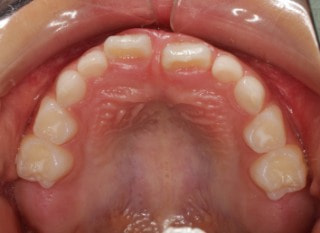

小児期の第二段階

治療中